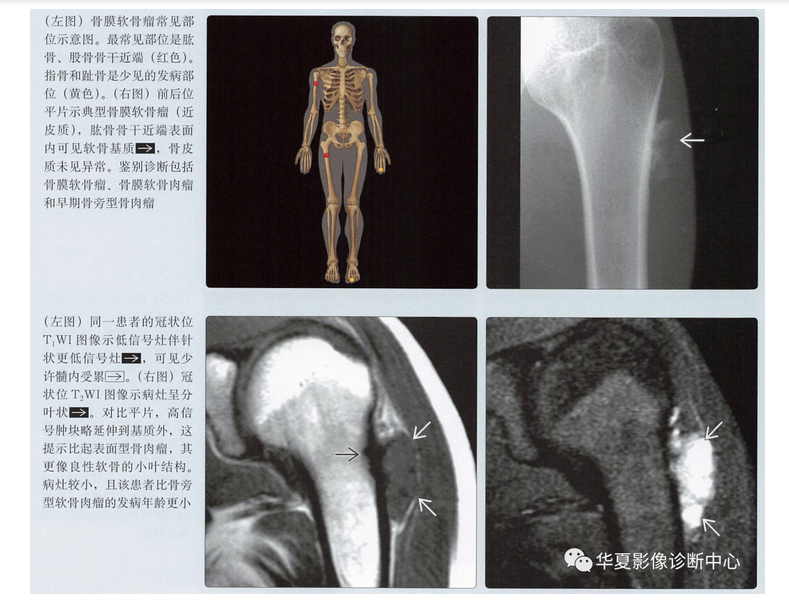

MR表现

- 病灶的结节状形态

- T1上等或低信号

- T2上高信号

- 不均匀强化,通常呈边缘强化

- 髓内累及(20%)

- 髓内水肿(20%)

- 不规则软组织肿块(30%)

骨膜软骨肉瘤

- 很少见的表面型软骨肉瘤

- 与骨膜软骨瘤发病部位相同

- 通常为低度恶性,因此可能不会出现明显侵袭性

- 几乎与骨膜软骨瘤影像表现相同

- 类似的MR特征

- 低级别软骨形成小叶结构,液体敏感序列上呈高信号

- 边缘强化,伴比较小的软组织肿块

- 与骨膜软骨瘤没有可靠的鉴别点,但是

- 病灶可能比大多数骨膜软骨瘤大

- 比骨膜软骨瘤发病年龄略大